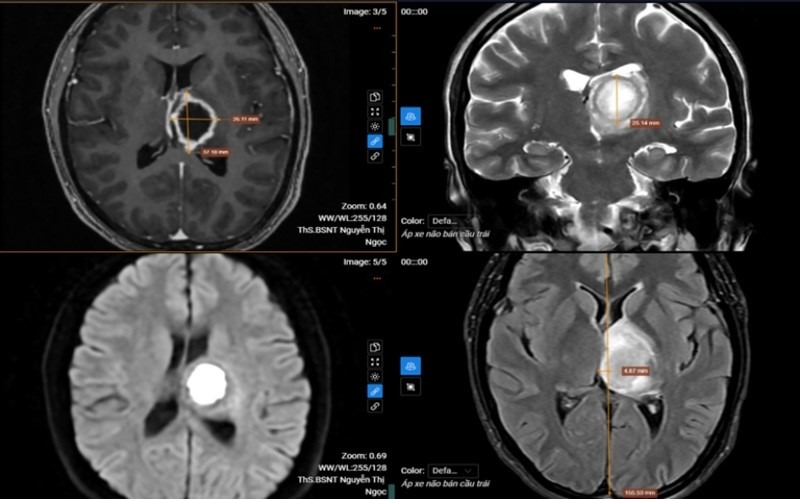

| Kết quả MRI phát hiện tổn thương khu trú tại vùng đồi thị - vành tia bên trái. |

Đặc biệt, khi chụp cộng hưởng từ (MRI) sọ não, các bác sĩ phát hiện tổn thương khu trú tại vùng đồi thị, vành tia bên trái. Tổn thương dạng dịch có kích thước khoảng 26x37x25 mm, ranh giới rõ nhưng bờ không đều.

Phần trung tâm hạn chế khuếch tán, sau tiêm thuốc đối quang từ xuất hiện viền ngấm thuốc. Vùng xung quanh có phù não, gây hiệu ứng khối và đẩy lệch đường giữa sang phải khoảng 5 mm. Kết quả cộng hưởng từ phổ (MRS) ghi nhận giảm Choline và NAA, đồng thời tăng Lipid và Lactate, đặc điểm thường gặp trong các ổ áp xe não.

Sau khi hội chẩn chuyên môn, các bác sĩ kết luận bệnh nhân mắc áp xe não bán cầu trái và được chỉ định nhập viện điều trị nội trú theo phác đồ chuyên khoa nhằm kiểm soát nhiễm trùng và hạn chế các biến chứng thần kinh.